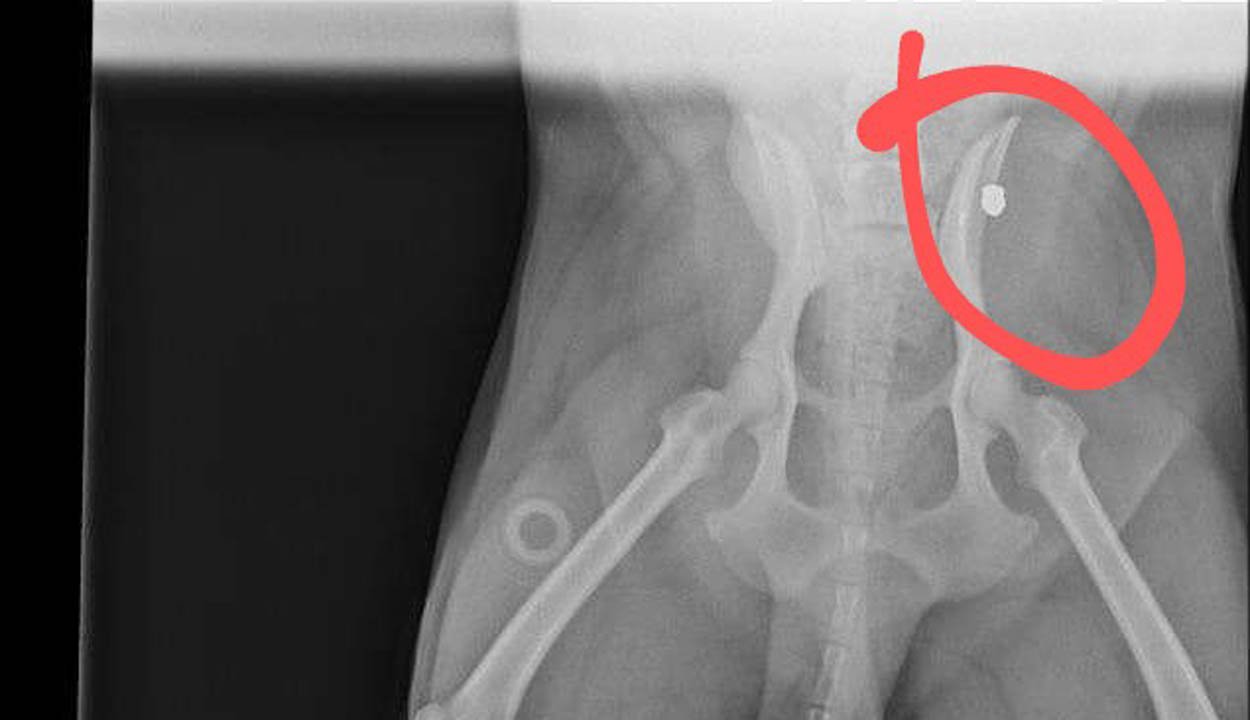

Igyártó Nándor, a kutya megmentésében segédkező állatvédő lapunknak elmesélte, a kutyának pénteken kellett volna németországi örökbefogadóihoz utaznia, ám időközben fura dolgot, pontosabban egy golyót találtak a testében, így egyelőre felfüggesztették az örökbefogadási folyamatot.

– Peti rossz sorsáról engem egy hölgy értesített, ő nevezte el így az ebet, és hát maradt a név. Nem ritka, hogy „magyar” kutya kerül külföldre, és az ottani gazdák, miután közlik velük a négylábúak addigi neveit, végül úgy döntenek, megtartják, mert hangzatosnak találják, és a kutya is megszokta már. Szóval Petit az elkobzás után a szépmezői menhelyre vitték a hatóságok, aztán közbejárásommal a brassói Animals Need Us állatvédő egyesülethez került, innen utazott volna pénteken a németországi örökbefogadóihoz. Időközben az egyesület elnöke észrevette, hogy a kutya furán mozgatja egyik lábát, így megröntgenezték, és kiderült, hogy egy golyó van a csípőjében. Hihetetlen, hogy mennyi kínon ment át ez a szegény állat – számolt be az állatvédő.

A kutyát komolyabb vizsgálatoknak vetik alá, hiszen meg kell állapítani, hogy a betokosodott golyó veszélyt jelent-e az egészségére, ki tudják-e műteni a valószínűleg légpuskával belé lőtt fémdarabot.

– Várjuk az örökbefogadó válaszát is, hiszen az is előfordulhat, hogy ő vállalja a kutya gyógyítását, ha műtétre lenne szükség – összegzett Igyártó.